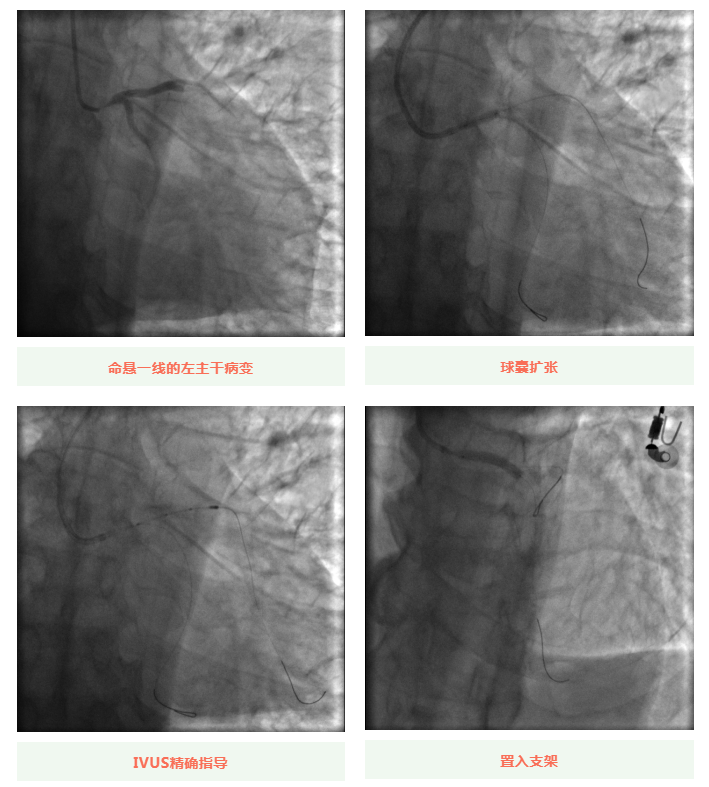

心血管內(nèi)科副主任徐先進在主任助理農(nóng)彥林和主任汪念東的配合下行冠狀動脈造影,結(jié)果如術(shù)前判斷一致,左主干重度狹窄,患者命懸一線。對團隊緊急處置非常信任的李阿姨,毫無疑慮地聽取了術(shù)者的建議,同意在血管內(nèi)超聲(IVUS)的精準(zhǔn)指導(dǎo)下,在患者左主干內(nèi)植入一枚支架,成功拯救了患者的生命。